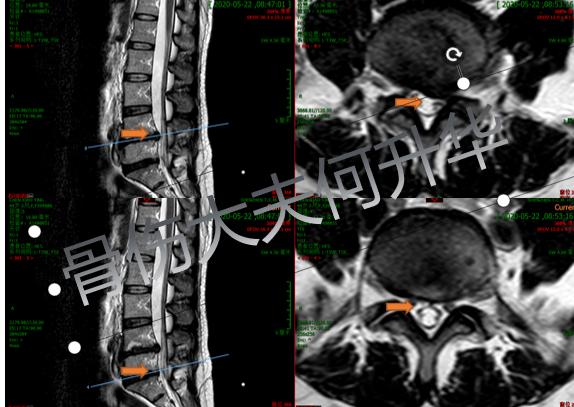

入院后MRI横断面提示腰4/5左侧

椎间盘突出,腰5骶1椎间高度丢失